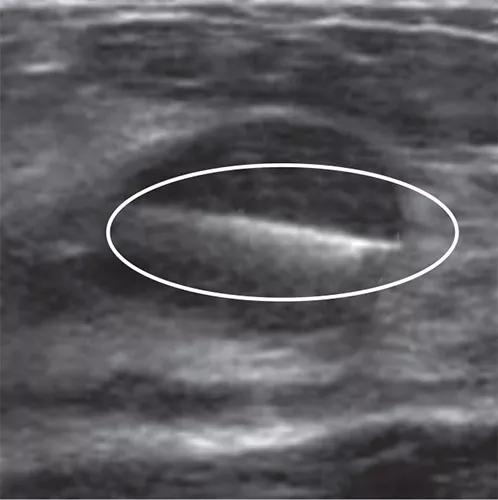

Tumark Professional Q and U markers are sandblasted nitinol, designed to provide outstanding visibility in ultrasound, and excellent visibility under mammography at deployment. In 85% of marker placements, physicians stated the ultrasound visibility was good to excellent upon deployment.2

Intelligent design on all six distinct, easily identifiable shapes1 provides sound tissue fixation. Non-resorbing material expands into marker shape upon deployment to improve the stability of the anchor following a breast biopsy procedure.

In the initial data collection study: 91% of markers placed under ultrasound did not migrate, as measured on the post-procedure mammogram.1 In 9 out of 10 cases the marker deployed accurately in ultrasound to the intended area.1